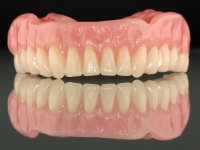

After clinical and radiological evaluation several rehabilitation plans were discussed with the patient. It was decided to extract the remaining lower teeth and do an overdenture retained by two dental implants with the locator attachement system to achieve a better retention and stabilization of the lower denture.

Two dental implants were planned in the CBCT scan, in the area of the inferior canines. The dental extractions were performed and, simultaneously, the alveolar crest was flattened and the implants were placed. Three issues were considered while implant placement: parallelism of the axis, same height of the implant’s neck, and same position in the coronal plan. This 3D insertion is essential to have a good retention of the overdenture in the future. Patient’s removable denture was fixed in the dental lab, to include the extracted teeth, and a soft-tissue relining was done over the healing abutments. After the osseo-integration period, a first impression was done with an open-tray and a doble-mix technique. This dental impression allowed the production of screwed wax-rims and an individual tray for a functional impression. A second impression, final, was done with an individual tray with a monophasic silicone. The occlusal wax-rims were correct in the mouth according to the full denture guidelines. Special care was taken with the occlusal vertical dimension and the support in the soft-tissues. A silicone bite registration material was used to better defined the intermaxillary relations. Teeth set-up was done in the dental lab with the selected tooth color. Due to the fact that the base was screwed to the dental implants, the teeth set-up was functionally evaluated in the mouth. Another silicone bite registration material was used to allow final occlusal adjustments. Finally, the locators were screwed and the retention nylons were selected according to the patient needs.